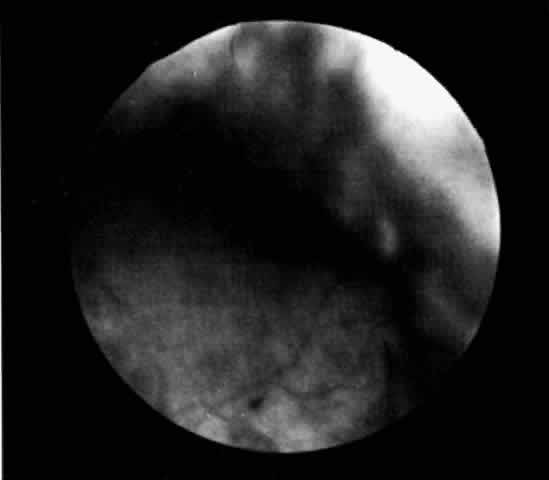

| The presence of certain clinical characteristics may assist in the diagnosis

of a ciliochoroidal effusion (Table 1). One clinical feature is choroidal edema. Choroidal edema may resemble

a retinal detachment to a hasty observer; however, darkness of the uvea, lack

of tremulousness, and normal retinal vessels indicate a probable

uveal process (Fig. 1). The effusion may extend under the pars plana, allowing visualization

of the ora serrata without scleral depression (Fig. 2).9 As shown in Figure 2, the surface of the elevation is convex and smooth, with a solid appearance

and a homogeneous grayish color. A shallow anterior chamber and

a low intraocular pressure may also suggest the diagnosis. Myopia in the

presence of anterior displacement of the lens-iris diaphragm may be

another diagnostic clue.10,11